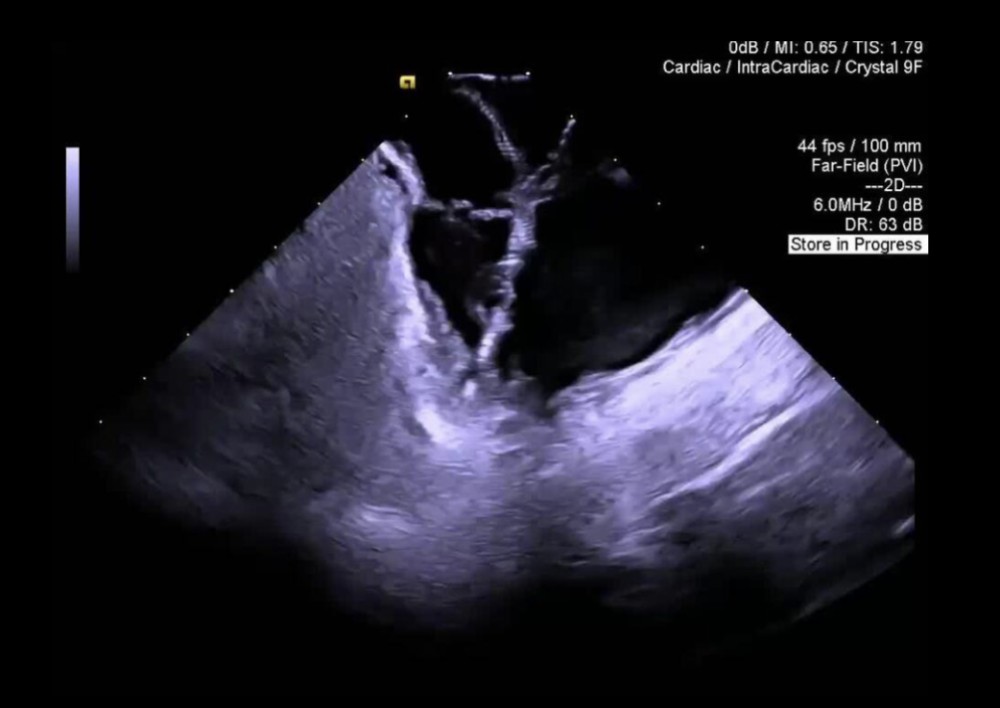

İntrakardiyak Ekokardioqrafiya (ICE)

AcuNav 8F+ — böyüklər üçün intracardiac

AcuNav 10F+ — pediatrik intracardiac

AcuNav Volume ICE — 3D intracardiac